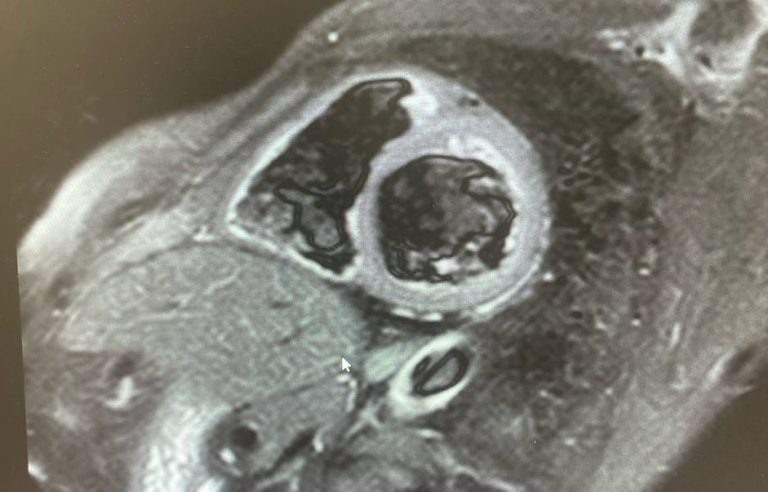

В Оренбургской областной клинической больнице имени В. И. Войнова за 2025 год выполнено 99 исследований МРТ сердца для 50 пациентов. Это направление стало одним из ключевых в развитии региональной кардиодиагностики. Врачи подчеркивают: за этими цифрами — не просто отчёт, а месяцы подготовки, обучение персонала и стремление вывести медицинскую диагностику в Оренбуржье на новый уровень. Подготовка к запуску исследования началась ещё в 2024 году. Команда рентгеновского отделения при поддержке администрации больницы пригласила специалистов компании Canon, чтобы расширить базовую комплектацию оборудования и точно настроить протоколы для магнитно-резонансной томографии сердца. Первые тестовые исследования помогли откорректировать параметры, устранить неточности и выработать оптимальный режим работы оборудования. МРТ сердца считается одним из самых сложных и трудоёмких исследований в современной медицинской практике: оно требует высокой концентрации, занимает больше времени, чем обычная томог

Первым врачом-рентгенологом, прошедшим обучение, стал Фаил Кутлубаев. Позже к направлению присоединилась Анжелика Бузина. Повышение квалификации прошли и рентгенлаборанты — Наталья Бойко и Евгений Зелинский. Сегодня специалисты отдела уверенно диагностируют кардиомиопатии, миокардиты, постинфарктный кардиосклероз и другие сложные патологии сердца.

В планах отделения — дальнейшее развитие диагностических программ, в том числе обучение по патологиям клапанов сердца и выявлению опухолей.